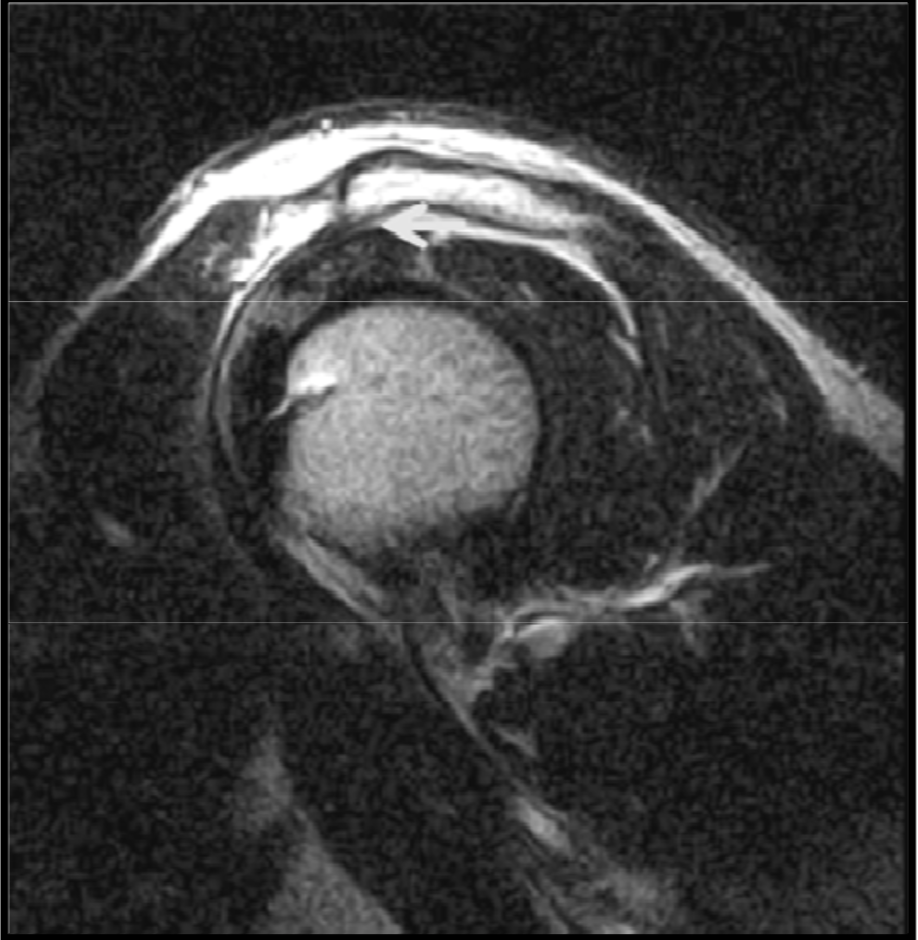

Os acromiale

variation anat normal